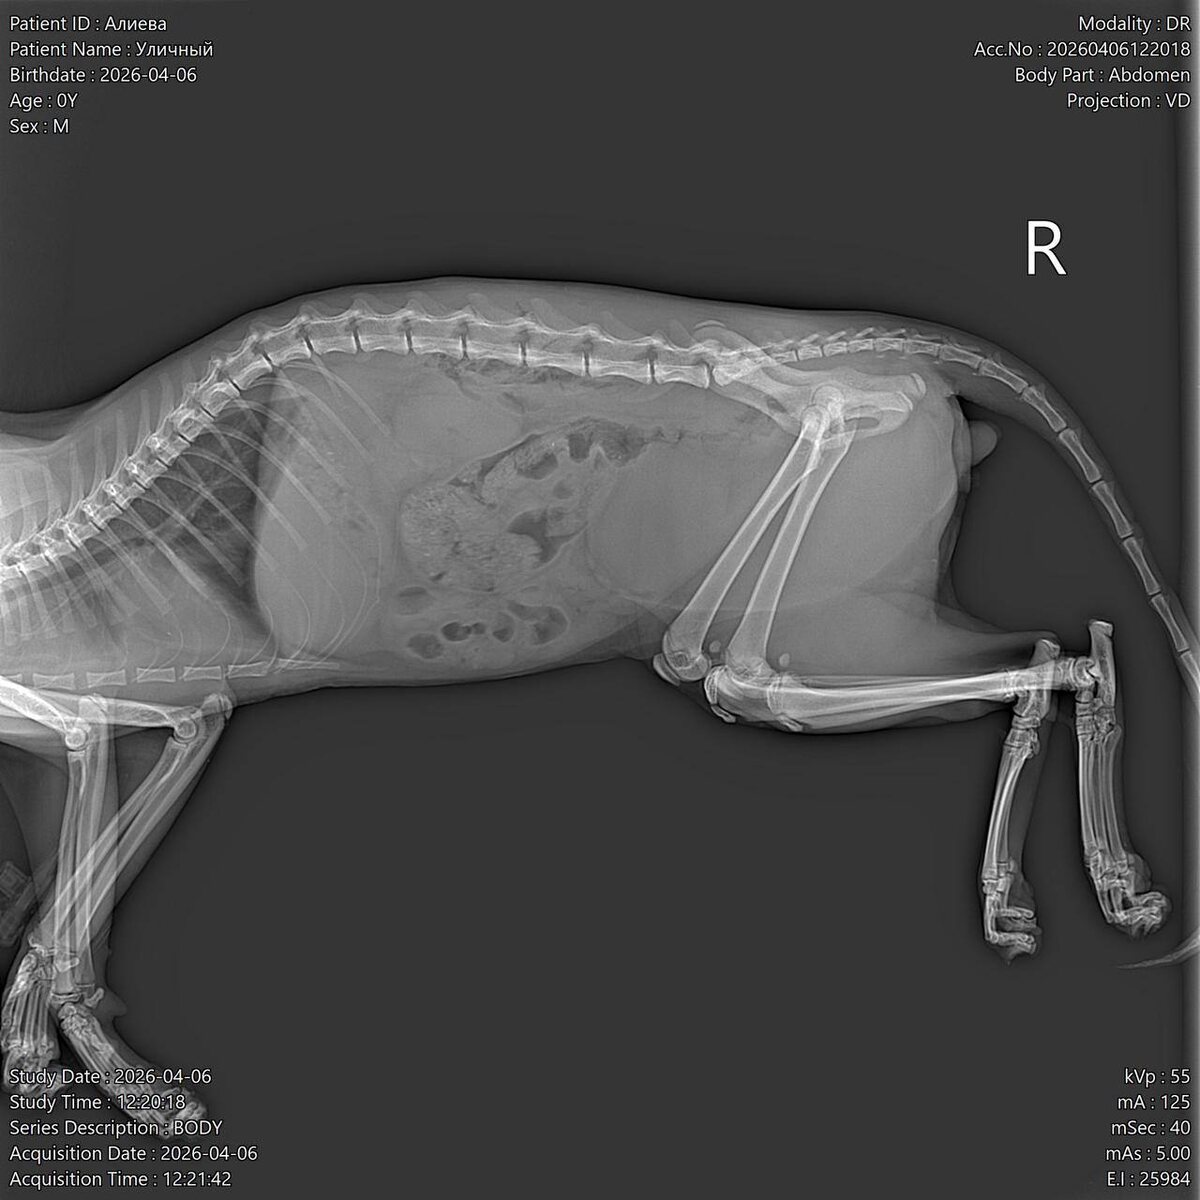

По рентгену слава Богу нет ничего страшного, повреждены только мягкие ткани.

Сейчас курс антибиотиков, покой и восстановление. 🙏🏼🙏🏼🙏🏼